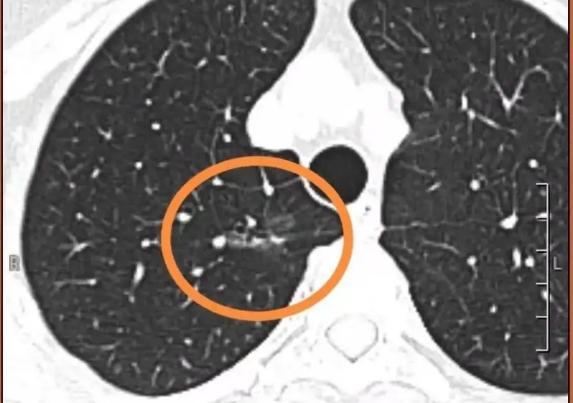

肺磨玻璃结节(GGN)指的是CT影像上,像磨砂玻璃质地的密度轻度增高的云雾状淡薄影。GGN中的磨玻璃成分对应的是病理上的鳞屑样生长方式,异常增生的上皮细胞或分化良好肿瘤细胞以鳞屑样方式生长而形成影像上的磨玻璃影。具体表现为增生的细胞沿现有的结构和肺泡壁生长而不侵犯基质、胸膜或血管,保持完整的肺泡结构,基底膜仅有轻度反应。它打破了恶性肺部肿瘤生长或倍增的“两年定律”,不遵守PET检查SUV值增高的规律,表现为非常明显的惰性生长的特点,直径倍增时间可长达3-5年。

肺磨玻璃结节(GGN)根据有无实性成分可分为纯GGN和混和型GGN。如果结节内只用磨玻璃成分,称为纯磨玻璃结节;如果既有磨玻璃成分,又含有实性成分,则称为混和型磨玻璃结节。

1伴有明显分叶、空泡、胸膜凹陷征或明显实性成分(如荷包蛋,中间厚、外周薄)的GGN提示可能恶性病变;